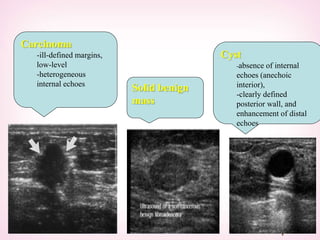

Carcinoma

-ill-defined margins,

low-level

-heterogeneous

internal echoes

Solid benign

mass

Cyst

-absence of internal

echoes (anechoic

interior),

-clearly defined

posterior wall, and

enhancement of distal

echoes